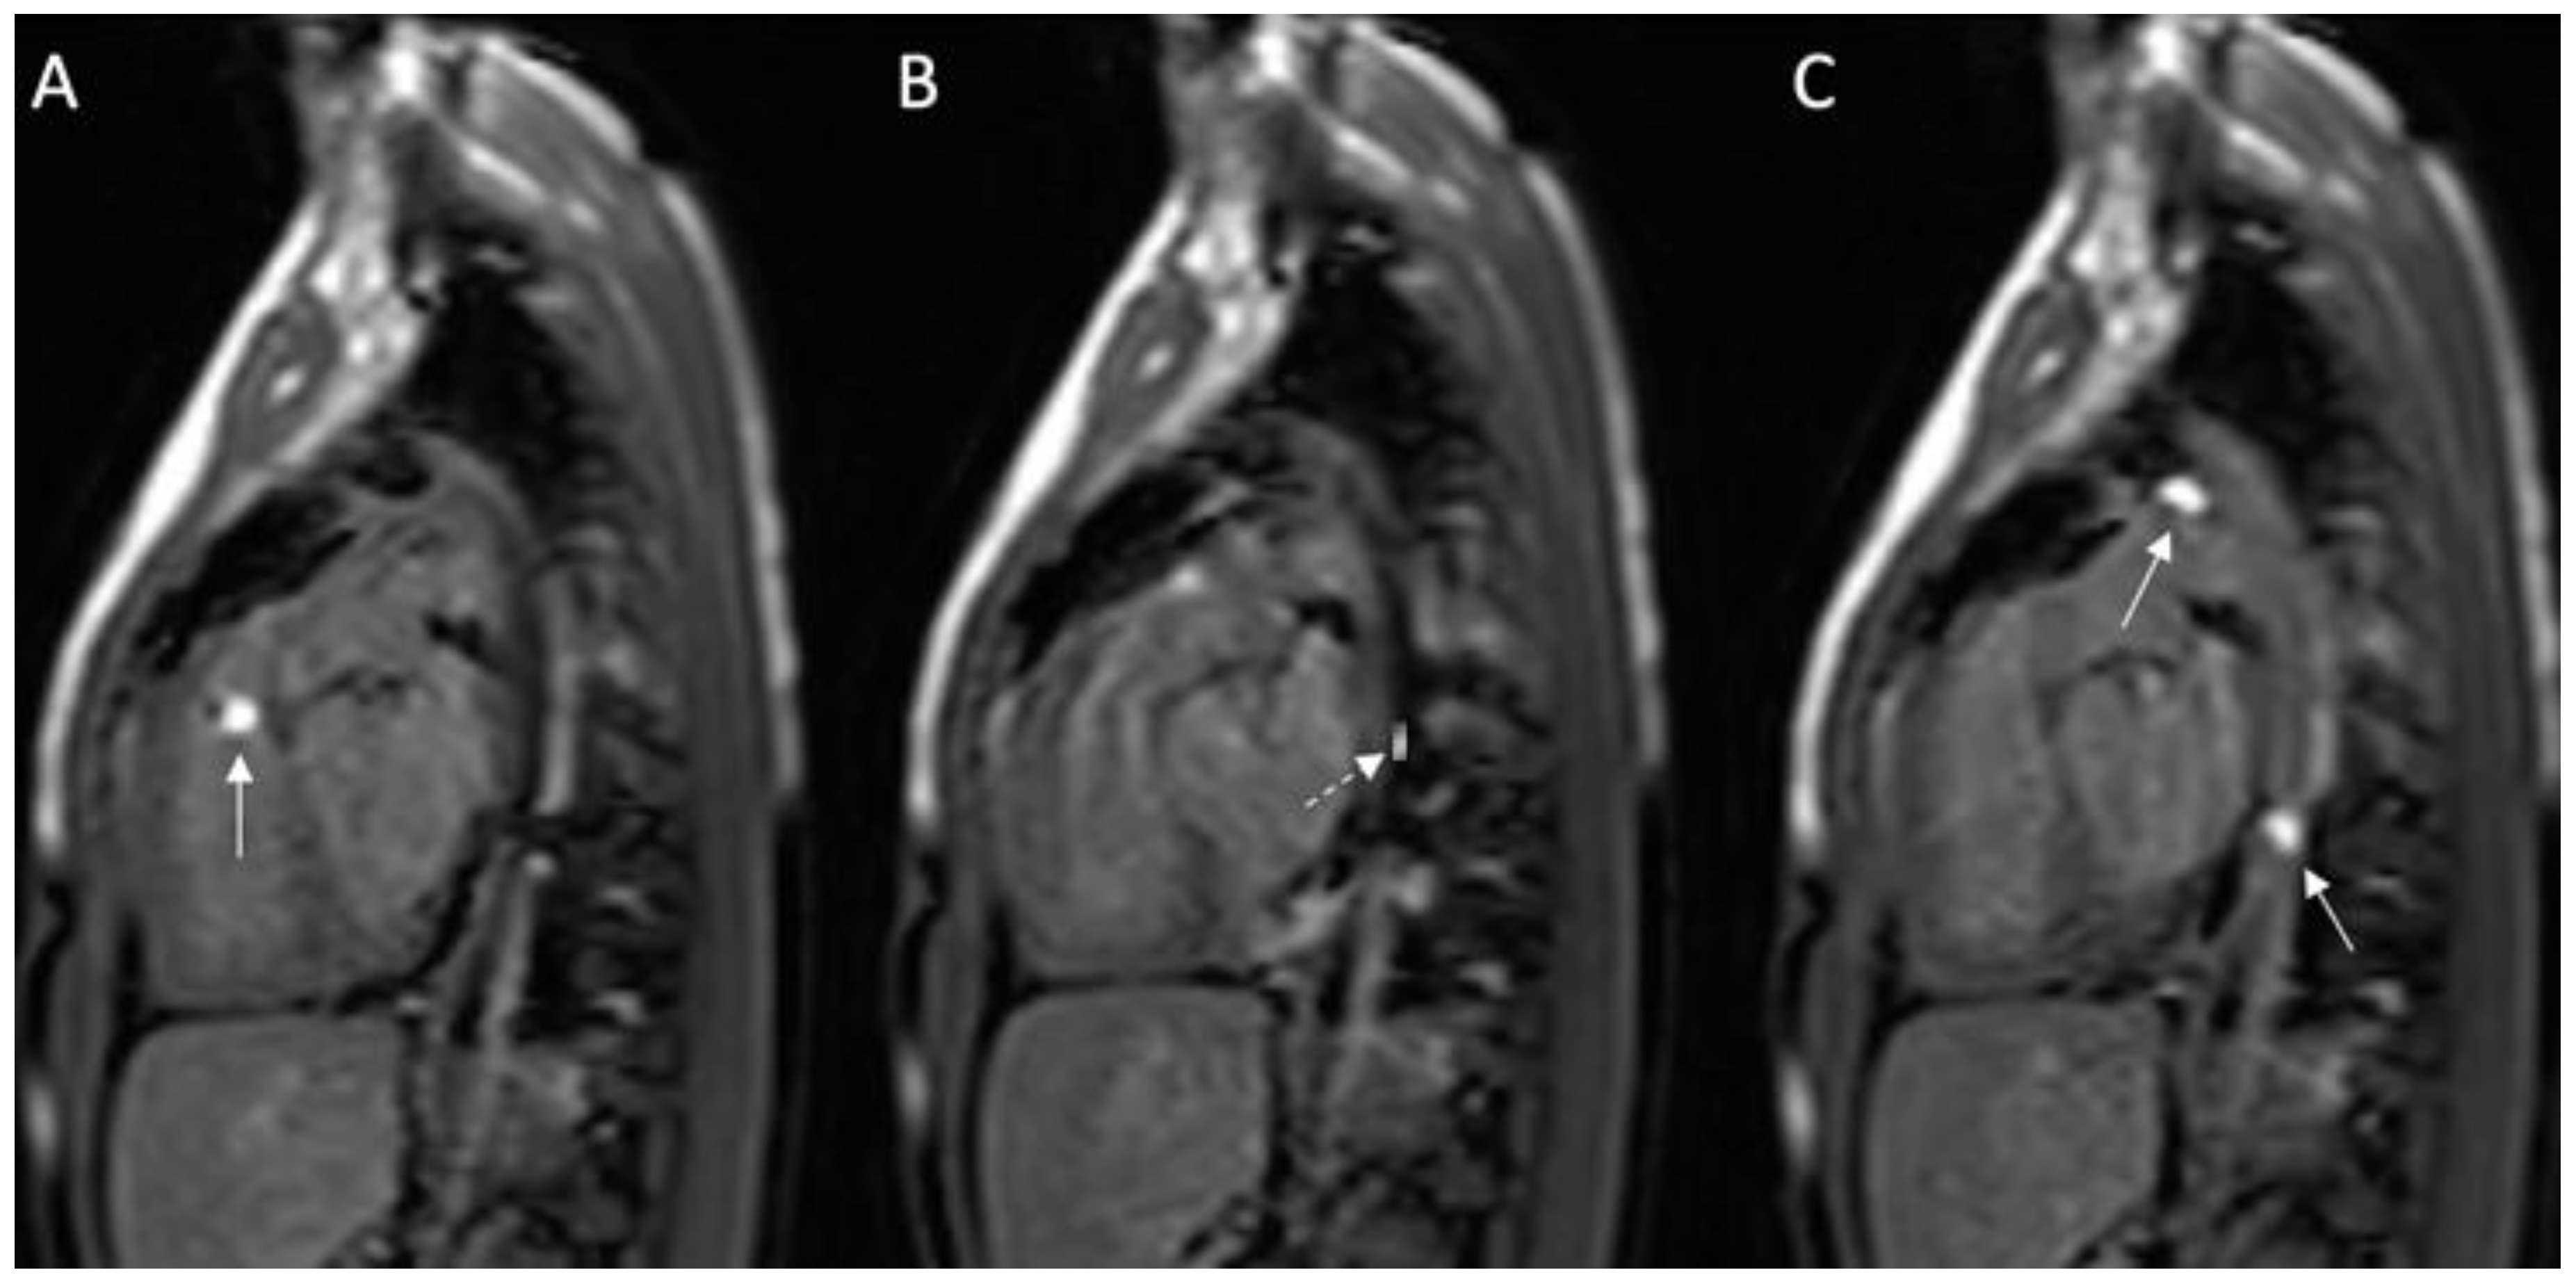

Figure 3.

Invasive cardiac magnetic resonance (iCMR) pulmonary hypertension evaluation environment. MR-conditional nitric oxide (INOmax DSIR@ Plus Delivery Systems, Mallinckrodt Pharmaceuticals, USA) (arrow) next to the Philips Ingenia 1.5 Tesla magnet.

Total pulmonary blood flow assessment was done by summing the flow in the right pulmonary artery (RPA) and the left pulmonary artery (LPA) distal to PDA entrance, the approach based on the assumption that total pulmonary flow can be more accurately quantified by measuring flow in each branch artery [9]. Cardiac output was calculated by measuring blood flow in the ascending aorta as previously described [10]. The total pulmonary blood flow was calculated using the measured RPA and LPA net antegrade blood flow volume [11]. A 6 French balloon wedge catheter was used to perform the CMR-guided RHC procedure. Using the Philips interactive scanning mode guidance (Philips Healthcare), the interventionalist advanced the gadolinium-filled balloon tip of the wedge catheter and MR-conditional guidewire (Emeryglide MRWire Nano4Imaging, Aachen, Germany) (Figure 4). Magnetic resonance imaging provided excellent soft-tissue contrast for completing the right heart catheterization, including 3D reconstruction of the aortic arch, PDA, and branch pulmonary arteries (Figure 5).

Figure 4.

(A–C): Series of images during the invasive cardiac magnetic resonance (CMR) in this case. (A) Gadolinium-filled balloon in right ventricular outflow tract (arrow); (B) MR-compatible wire placed prograde across the patent ductus arteriosus (PDA) into the descending aorta; (C) Two gadolinium-filled balloons positioned within the PDA and descending aorta. Solid white arrow: gadolinium-filled balloon; dashed white arrow: MR-compatible wire.